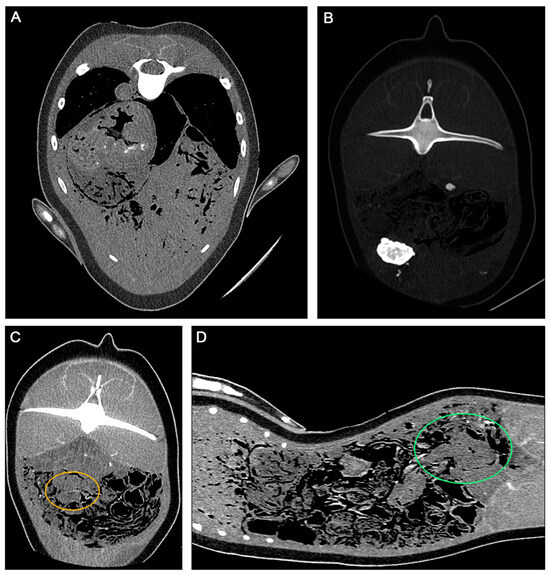

- Yuen, A.H.L.; Kim, S.W.; Lee, S.B.; Lee, S.; Lee, Y.R.; Kim, S.M.; Poon, C.T.C.; Kwon, J.; Jung, W.J.; Giri, S.S.; et al. Radiological investigation of gas embolism in the East Asian finless porpoise (Neophocaena asiaeorientalis sunameri). Front. Mar. Sci. 2022, 9, 711174. [Google Scholar] [CrossRef]

- Yuen, A.H.L.; Lee, S.B.; Kim, S.W.; Lee, Y.M.; Kim, D.G.; Poon, C.T.C.; Seo, J.-P.; Baeck, G.W.; Kim, B.Y.; Park, S.C. Fatal upper aerodigestive tract obstruction in an East Asian finless porpoise (Neophocaena asiaeorientalis sunameri): Findings in post-mortem computed tomography. Forensic Sci. Med. Pathol. 2023, 19, 1–8. [Google Scholar] [CrossRef]

- Gopireddy, D.R.; Soule, E.; Arif-Tiwari, H.; Sharma, S.; Kanmaniraja, D.; Jain, K.; Lall, C. Spectrum of CT findings related to bowel adhesions without bowel obstruction: A comprehensive imaging review. J. Clin. Imaging Sci. 2020, 10, 80. [Google Scholar] [CrossRef] [PubMed]